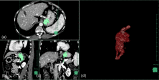

Methods: 57 consecutive patients who underwent balloon-occluded retrograde transvenous obliteration (B-RTO) for GV were divided into three groups with Hirota's grade by balloon-occluded retrograde transvenous venography. Hirota's Grade 1 patients were assigned to G1 group and underwent treatment with 5% EOI. Grade ≥ 2 patients prior to August 2015 were G ≥ 2 group treated with 5% EOI, and those treated thereafter were GERTO group. The amount of EOI used per unit GV volume (EOI/GV ratio), the times to embolization and recurrence rate of GV were evaluated.